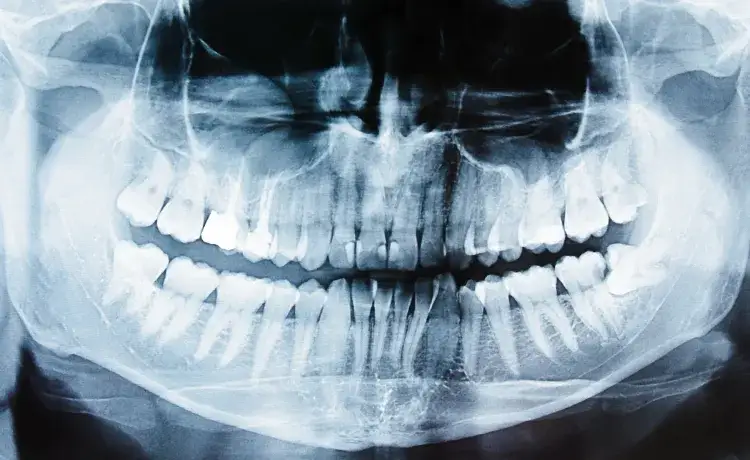

Ile korzeni ma ząb 5 górna? To pytanie nurtuje wiele osób, które chcą zrozumieć anatomię swoich zębów. Ząb 5 górna, znany również jako górny pierwszy trzonowiec, zazwyczaj ma trzy korzenie. Jednak u niektórych osób może występować ząb 5 górna z dwiema korzeniami. W rzadkich przypadkach można spotkać ząb z więcej niż trzema korzeniami, lecz najczęściej występujące liczby to właśnie dwa lub trzy.

Ząb 5 górna, który jest jednym z kluczowych zębów w jamie ustnej, zazwyczaj ma trzy korzenie. To właśnie te korzenie są odpowiedzialne za stabilność zęba oraz jego funkcję w procesie żucia. U niektórych osób można jednak spotkać przypadki, gdzie ząb ten ma dwa korzenie. Rzadko zdarza się, aby ząb 5 górna miał więcej niż trzy korzenie, co czyni go dość unikalnym w swoim rodzaju.

W kontekście zdrowia jamy ustnej, liczba korzeni zęba 5 górna ma istotne znaczenie. Korzenie te wspierają ząb, a ich struktura wpływa na jego funkcjonalność. Zrozumienie, ile korzeni ma ząb 5 górna, jest kluczowe dla osób dbających o zdrowie zębów oraz dla dentystów, którzy planują leczenie stomatologiczne.